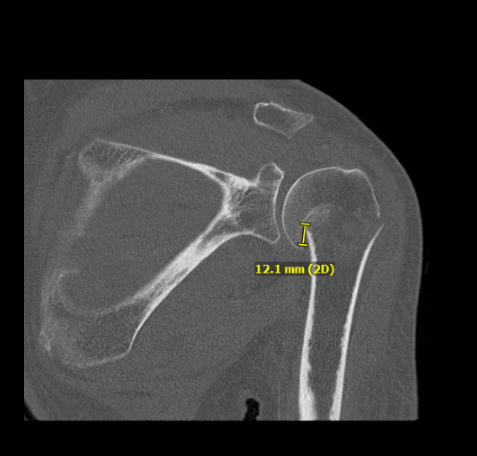

CT scan result also discussed to patient, comminuted proximal humeral fracture is impacted and slightly angulated fracture component at the surgical neck, slightly displaced fracture fragment at the greater tuberosity and a subtle nondisplaced fracture at the lesser tuberosity.

Bones are osteopenic. There is no evidence of bony bridging. There is a glenohumeral joint effusion.